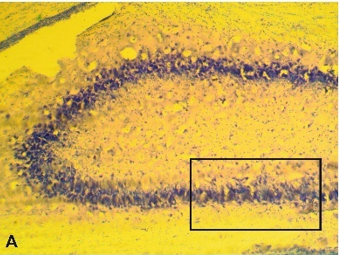

Histological Study

We found that rotenone caused profound morphological changes in the hippocampal cells. Although neurons in the hippocampus retained staining intensity after rotenone toxicity, they were wrinkled. The hippocampal cells exhibited irregular staining [18]. The structure of the Nissl substance was disrupted. Some neurons showed signs of edema. There was a redistribution of tigroids to the periphery of some neurons. Pyknosis of most neurons was observed in the rotenone group (Figure 3). Pyknotic neurons are characterized by small size, well-defined oblong forms, and intense chromatophilic substances (or Nissl bodies) in the cytoplasm. Their nuclei had a diffuse basophilic appearance, an elongated or triangular form, and their nucleoli were almost invisible.

Figure 3. Nissl staining of hippocampal neurons in the rotenone group. Scale: A-C 100 µm.

As shown in Figure 4, DMSO group neurons were characterized by round to oval nuclei. The chromatophilic substances of these neurons were evenly distributed in the cytoplasm as lumps with light spaces. The presence of both hyperchromic and hypochromic-stained cells characterizes the morphology of the hippocampus in the DMSO group. The processes are traced at a short distance, cell contours are visible, and light nuclei can be observed in some neurons. In general, the state of nervous tissue is characterized by varying degrees of functional activity due to the presence of hyperchromic neurons (Figure 4).

Figure 4. Nissl staining of hippocampal neurons in DMSO-treated rats. Scale: A-C 100 µm.

In this study, we examined how three weeks of rotenone and DMSO treatment affected hippocampal neuronal activity and neuronal response properties in rats. The toxic effects of rotenone on DMSO-treated hippocampal CA1 and CA3 cells were compared. We found that the DMSO group had fully developed neurons in the hippocampus, replete with nucleoli that were easily visible, faintly colored cytoplasm, and orderly organization. The rotenone group, on the other hand, had notable cell shrinkage, amorphous cell morphology, cell membrane shrinkage, pyknotic and darkly pigmented nuclei, loosely distributed hippocampus cells, fewer pyramidal cells, and fewer Nissl bodies. Pyramidal cells and Nissl bodies in the hippocampus CA1 and CA3 areas of rats given rotenone therapy dramatically improved after DMSO treatment (Figures 3 and 4).